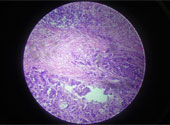

Hormonul sexual masculin, testosteronul, este un inductor puternic al creşterii şi dezvoltării tumorilor de la nivelul prostatei. Enzalutamida blochează în mod eficient receptorii androgenici (receptori nucleari citoplasmatici), manifestând totodată şi acţiune de inhibare asupra translocării acestuia şi interacţiunii sale cu ADN-ul. Ca urmare a blocării receptorilor androgenici, studiile in vitro şi cele preclinice au arătat că enzalutamida scade proliferarea, induce apoptoza celulelor tumorale prostatice şi reduce volumul total al masei canceroase. Principalul său metabolit (N-desmetil-enzalutamida) a prezentat acţiune in vitro similară compusului părinte.

Eficacitatea şi siguranţă Xtandi® au fost testate în cadrul unui studiu clinic de faza III multicentric, randomizat, placebo-controlat, pe un număr de 1.199 de pacienţi cu mCRPC. Din studiu au fost excluşi pacienţii cu istoric de convulsii. Principalul obiectiv al studiului a fost stabilirea perioadei medii de supravieţuire în comparaţie cu grupul de control: 18,4 luni pentru grupul tratat cu Xtandi® versus 13,6 luni pentru grupul placebo.